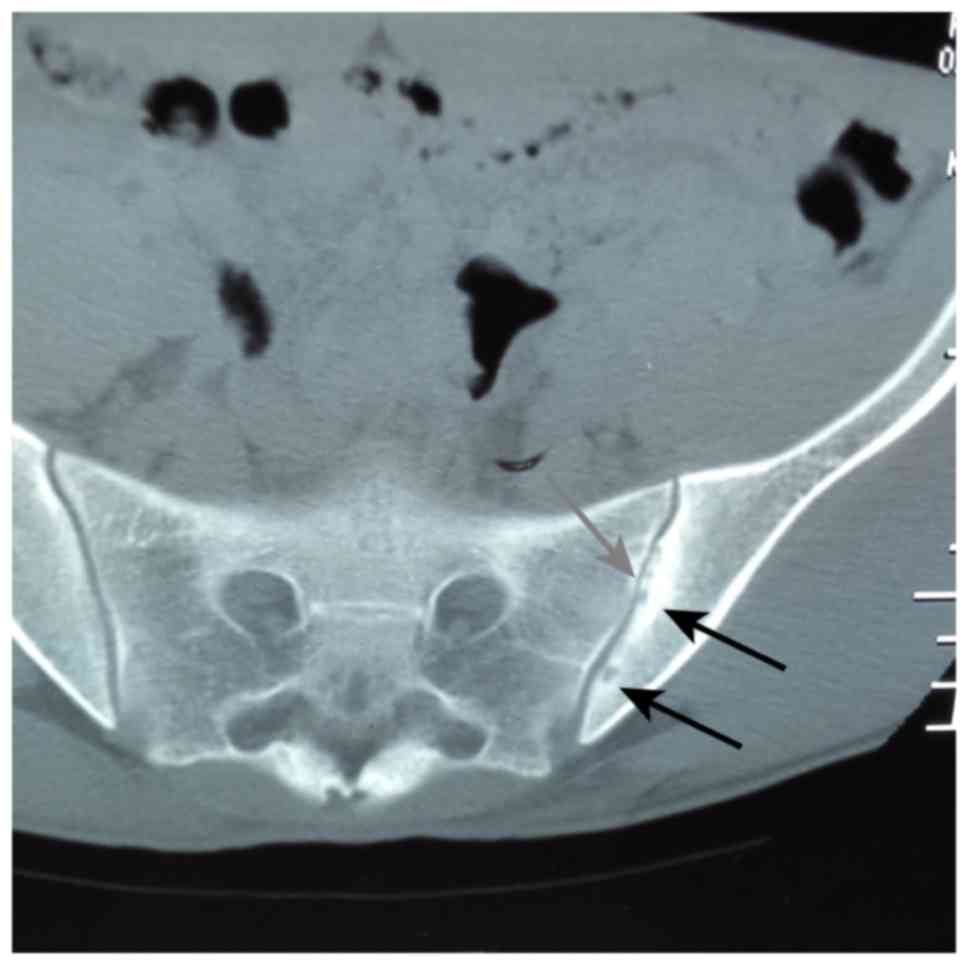

Although the risk of developing CML following repeated exposure to chest radiography and CT was of concern, a pelvic CT scan was ultimately performed on February 16, 2015 to confirm the diagnosis of AS (Fig. 1). The scan revealed bilateral narrowing of the sacroiliac joints in addition to bilateral cystic changes, which were more apparent at the surface of the left sacroiliac joint.

Figure 1.

Computed tomography image of the narrowing of the gap in the bilateral sacroiliac joint, and cystic changes in the bilateral iliac bones. The grey arrow indicates narrowing of the sacroiliac joint on the left. Cystic changes and damage were more apparent at the surface of the left sacroiliac joint (black arrows).

The patient visited the physician due to pneumothorax; initially, only chest CT scans and chest X-ray data were available. Pelvic CT scanning was not conducted until February 16th, 2015, when it was performed to confirm the diagnosis of AS (Fig. 1). That scan revealed the bilateral narrowing of the sacroiliac joints, in addition to bilateral cystic changes, which were more apparent at the surface of the left sacroiliac joint. The possibility that imatinib caused the occurrence of AS was rejected for the following reasons. Firstly, neither the location nor the nature of the pain changed; secondly, following commencement of imatinib treatment there were no evident changes in the patient's symptoms: Thirdly, the pelvic CT scan was performed just 7 months after the initiation of imatinib treatment; lastly, as no reports of imatinib-induced AS could be located in the literature, we considered this eventuality to be unlikely.